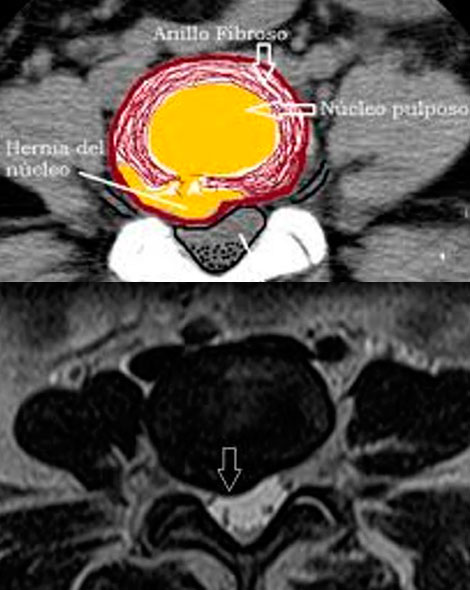

HERNIA DEL DISCO LUMBAR

La hernia discal es una enfermedad en la que parte del disco intervertebral (núcleo pulposo) se desplaza fuera de su lugar y como consecuencia comprime la médula espinal o alguna raíz y produce dolor, entonces es cuando puede hablarse de auténtica hernia discal.